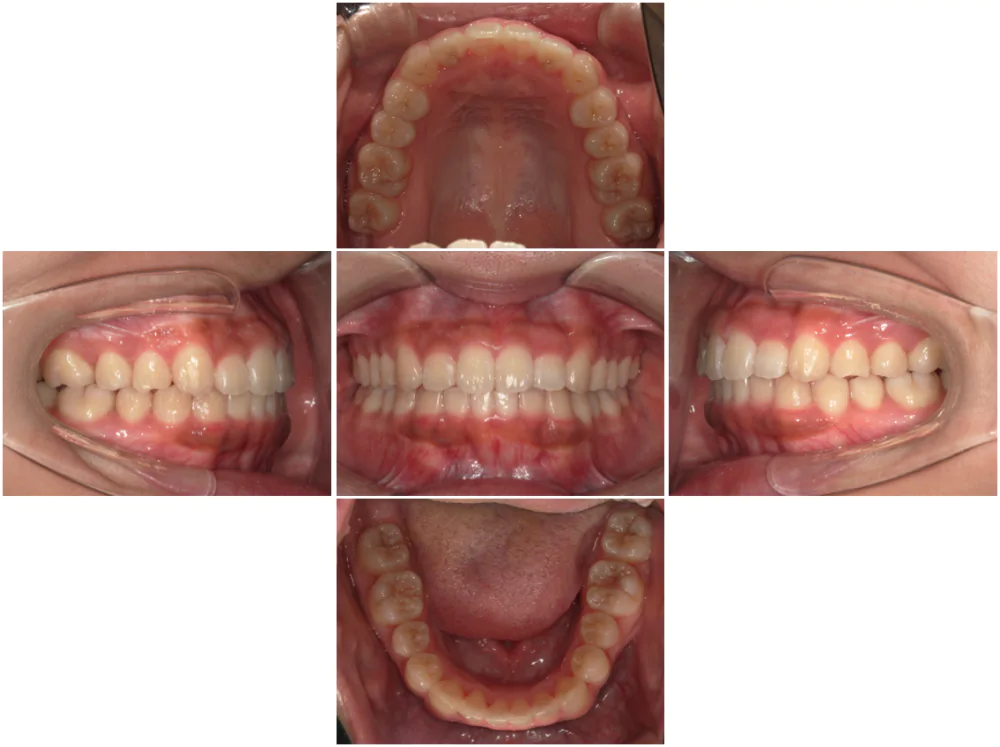

症例1

| 来院時の主訴 |

全体的なガタガタを治したい。

できれば抜歯はしたくない。

歯並びを気にせず笑えるようになりたい。

| 医院での対応や適用装置 | マウスピース矯正装置を使用して主訴であるガタガタを改善しました。 ガタガタの改善に必要なスペースの確保のために上あごの親知らずのみ抜歯を行いました。 |

| 通院期間 | 1年1ヶ月 |

| 通院回数 | 7回(治療中) |

| 治療費用総額 | 725,000円(税込) |

| リスクと副作用 | 矯正治療による歯の移動に伴う痛み、歯根吸収、虫歯 |